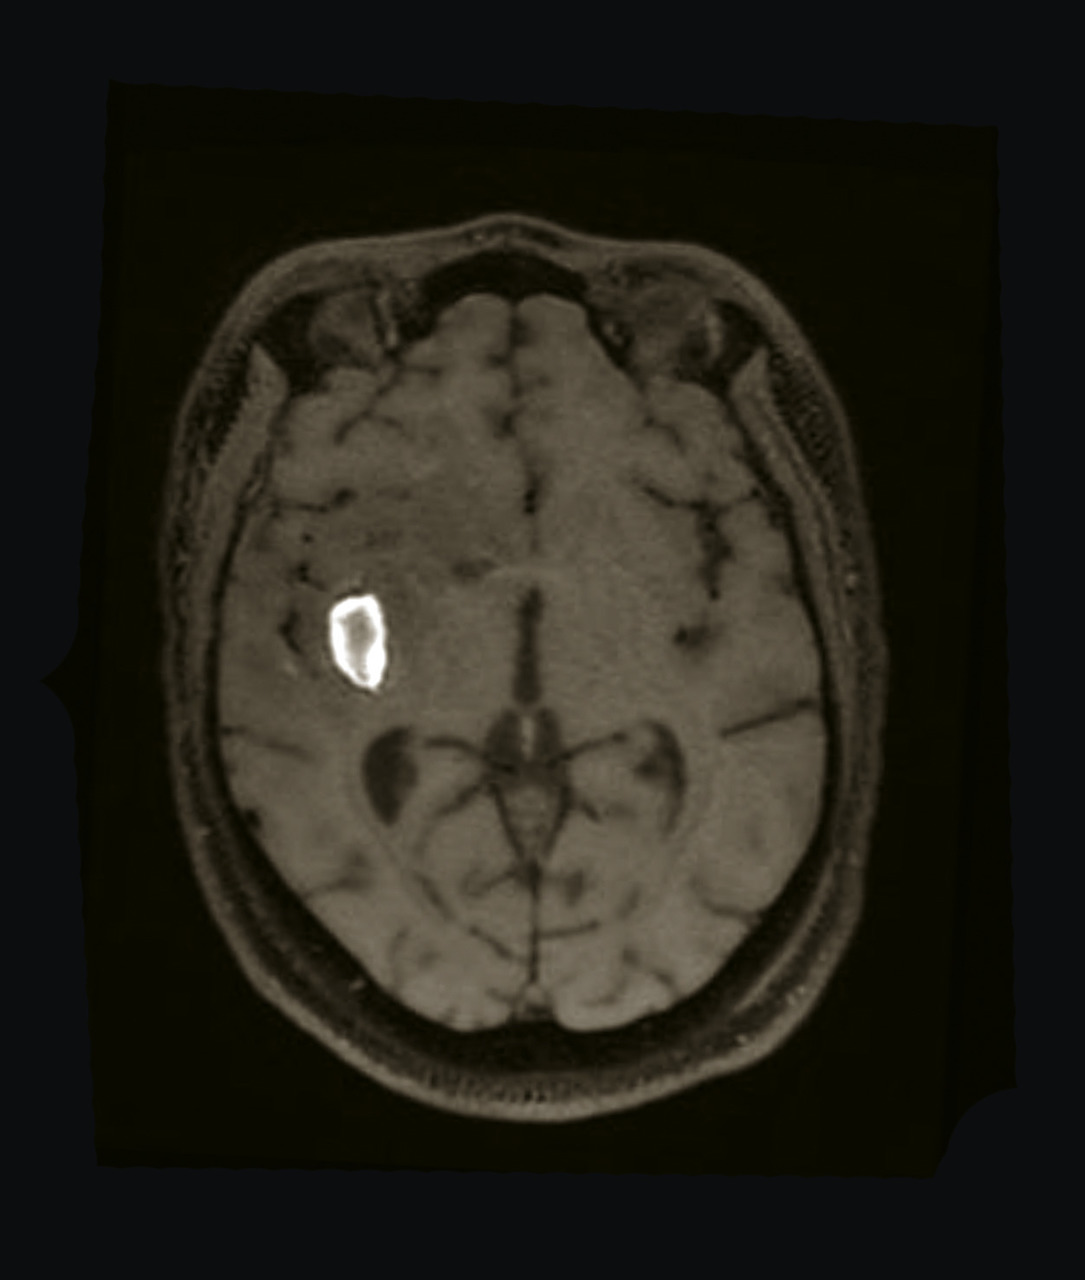

• un abcès cérébral (fig. 4) en présence d’un syndrome fébrile, d’un foyer infectieux, en particulier quand la prise de contraste est annulaire, un tuberculome en cas de contage ou terrain à risque ;